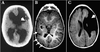

What is seen on the brain scans of a baby suffering from a congenital CMV infection?

Periventricular calcification